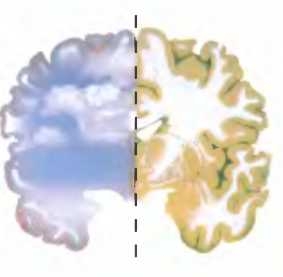

Когда в правое полушарие пациента с разделенным мозгом поступают изображения безмятежных картин, это вызывает у него эмоциональную реакцию, даже если он не осознает, что он видит.

В одном из своих экспериментов Гаццанига и Леду показывали правому полушарию пациентки с разделенным мозгом ряд видеороликов, в числе которых были кадры о том, как один человек толкал другого в огонь. При этом V. Р. не осознавала, что именно она видела, точно так же как N. G. в проведенном ранее эксперименте Роджера Сперри не осознавала, что видела ложку. Испытуемая рассказывала экспериментатору: “Кажется, я видела белую вспышку и, может быть, какие-то деревья, с красными листьями, как будто осенью... Не знаю, почему, но мне страшно... Что-то я нервничаю. Мне здесь не нравится... А может, это вы сделали так, чтобы я разнервничалась?” Затем она понизила голос и доверительно сообщила экспериментатору: “Я знаю, мне нравится д-р Гаццанига, но сейчас он меня почему-то пугает”. Бессознательные эмоциональные реакции подобного рода наблюдались и в тех опытах, где правому полушарию демонстрировали, напротив, приятные образы. Гаццанига и Леду установили, что просмотр правым полушарием роликов, показывающих прибой на океанском берегу, зеленый лес и тому подобное, вызывал у испытуемых спокойствие и безмятежность.